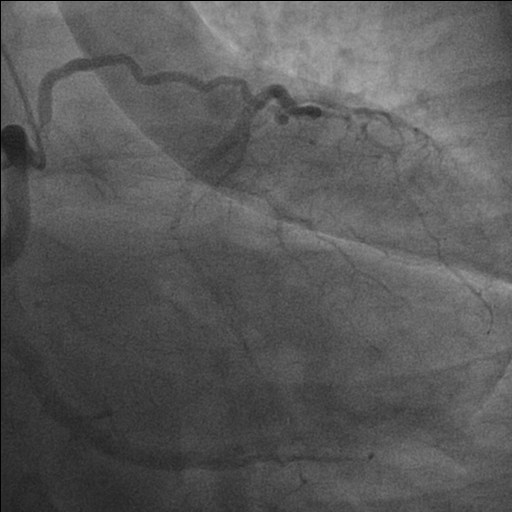

Background: Congenital absence (agenesis) of the left main coronary artery (LMCA) is an exceptionally rare coronary anomaly. Its coexistence with dilated cardiomyopathy (DCM) is scarcely reported, and the pathophysiological relationship between these conditions remains uncertain. Case presentation: A hypertensive female patient with multiple cardiovascular risk factors presented with exertional angina, palpitations, dyspnea on moderate exertion, and asthenia. Transthoracic echocardiography revealed mild left ventricular (LV) dilation with borderline systolic function and reduced global longitudinal strain, consistent with hypertensive heart disease. Coronary computed tomography angiography showed congenital absence of the left coronary artery, with compensatory collateral circulation originating from the conus branch supplying the anterior LV wall. Invasive coronary angiography confirmed the absence of the LMCA, a dominant right coronary artery, and collateral flow to a hypoplastic left anterior descending artery and the circumflex artery. Cardiac magnetic resonance imaging demonstrated preserved biventricular volumes and function, mild regional wall motion abnormalities, and subepicardial delayed gadolinium enhancement with a non-ischemic pattern in the mid-basal lateral wall. At follow-up, echocardiography showed progression to mildly reduced LV systolic function (LVEF 45%), consistent with ischemic–hypertensive cardiomyopathy. The patient’s twin sister, affected by dilated cardiomyopathy, underwent coronary CT angiography, which demonstrated anatomically normal coronary arteries. Given the familial occurrence of DCM, genetic testing was performed in both sisters to investigate a possible hereditary etiology. Discussion and conclusions: This case highlights the diagnostic complexity of concomitant LMCA agenesis and DCM. It remains unclear whether these conditions represent two independent entities sharing a genetic background or whether chronic myocardial hypoperfusion related to anomalous coronary anatomy may have contributed to LV remodeling. The presence of non-ischemic subepicardial fibrosis suggests additional mechanisms beyond epicardial coronary supply. Multimodality imaging and genetic evaluation are essential to clarify the relationship between congenital coronary anomalies, myocardial fibrosis, and ventricular dysfunction.